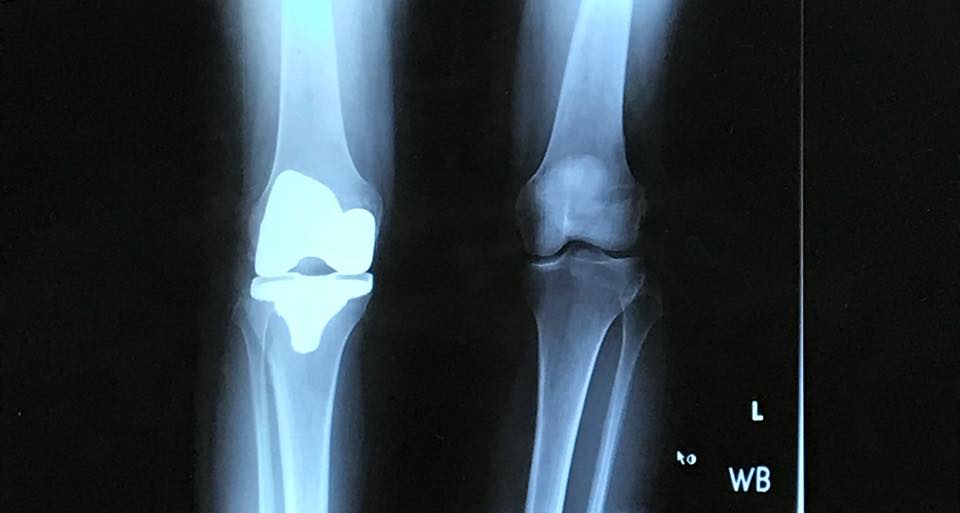

22405714_10105260919347393_3566541725643081823_n Published October 26, 2017 at 960 × 513 in Feeling Adult-ish After My Total Knee Replacement ← Previous